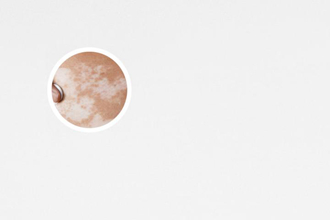

做一次氦氖激光治療白癜風(fēng)的費(fèi)用并不會(huì)很貴,通常幾百元到幾千元不等,具體費(fèi)用會(huì)根據(jù)治療部位的大小、治療頻率以及醫(yī)院的收費(fèi)標(biāo)準(zhǔn)而有所不同。但是,治療白癜風(fēng)是一個(gè)長(zhǎng)期的過(guò)程,需要持續(xù)治療,因此總的治療費(fèi)用會(huì)比一次治療的費(fèi)用要高得多。

治療的效果不錯(cuò): 氦氖激光可以刺激皮膚中的黑素細(xì)胞,促進(jìn)黑色素的生成,改善白斑的色素沉著。